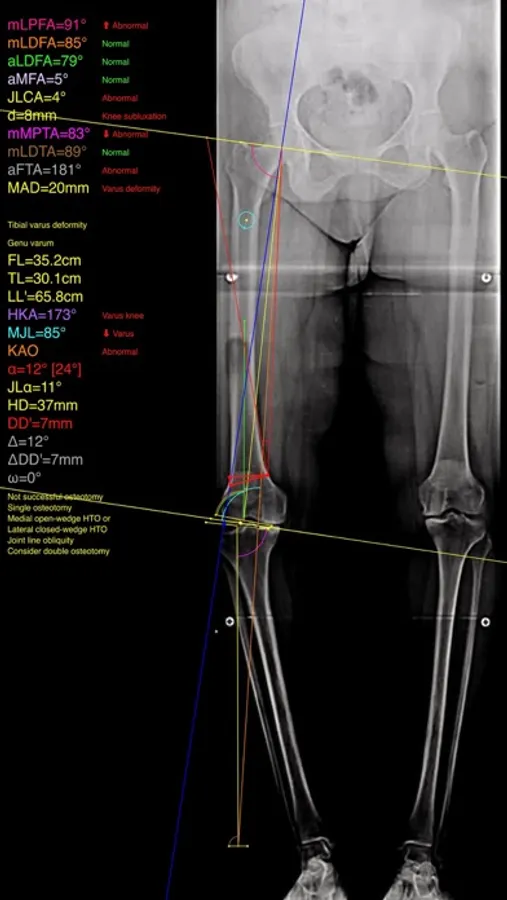

The app assists at preoperative correction planning by calculating :

-the amount of correction preoperatively by calculating the dimension of wedge size , the correction angle and osteotomy gap opening or closing.

-mechanical axis deviation (in mm) MAD, anatomical and mechanical femoral axes angle (aMFA),mechanical lateral proximal femoral angle (mLPFA), mechanical lateral distal femoral angle(mLDFA), joint line convergence angle (JLCA),mechanical medial proximal tibial angle (mMPTA), Mechanical lateral distal tibial angle (mLDTA), Hip Knee Ankle line (HKA) ,Mid joint line (MJL) orientation.

-objectively the deviation or deformity in the frontal plane (varus or valgus) and differentiate the level of deformity (femoral and or tibial origin) and according to measured angles objectively suggest where indicated, medial or lateral, open or closed-wedge distal femur osteotomy or high-tibial osteotomy or double osteotomies and avoiding unwanted obliquity of the joint line

-change the planned mechanical axis to pass at the preferred percentage (Fujisawa point) after evaluation of the residual cartilage thickness left on the involved compartment.

select the location of hinge point of correction osteotomy for planning of varus or valgus corrections

-evaluate in real time the success of intended osteotomy by evaluating the kinematic alignment of the knee (KAO), avoiding residual joint obliquity or malalignment.

-measure the correction angle adjusted due to ligament instability and preoperatively calculate the height of osteotomy gap opening.

-pressing + or - button, one degree of correction is added or subtracted respectively and the second plane of osteotomy emerges and printed in screen real offering real time simulation of the wedge osteotomy in an instant to comprehend in real time what parameters are affected and modify favourably the correction angle. All above mentioned angles and all limp axes are redrawn and updated accordingly for the given new correction angle. The drawn schematic gives the impression of settings act as a whole interchangable interacting unit.

-to combine correction- Biplanar-, at coronal plane and sagittal plane (based on Hernigou 2001 calculations ) on tibia slope and provide the direction of the plane (ω angle) in which the osteotomy (open or closed) should be made ,the height the opening or closing wedge and the correction angle (Δ angle),